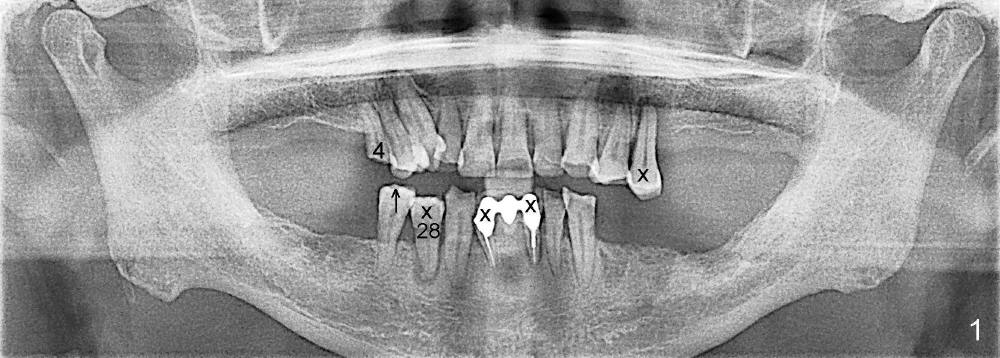

A 66-year-old man has poor dentition (Fig.1). Several teeth (x) including #28 need extraction and implants. The tooth #28 is extracted (Fig.2), followed by immediate implant (5x17 mm, Fig.3 I). There is more buccal gingival recession over the implant (Fig.4), which is less prominent 1.5 months postop (Fig.5). The definitive restoration is delivered less than 2 months postop (Fig.6), because of travel abroad. The patient agrees not to chew with the Emax crown. Five months later, he returns with chipped porcelain (Fig.7 arrowhead). It appears that immediate implant can survive early and over loading. More implants are necessary to share the masticatory loading. Since there is malocclusion, where to place implants appears to be critical (Model 3 30 4 5 6 7). There is no bone loss 4.5 years (Fig.8) or 5 years 8 months (Fig.9) post cementation.